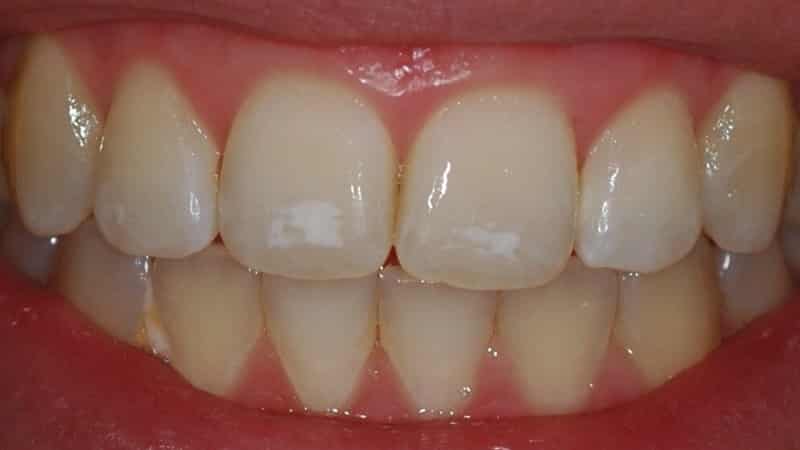

Многие люди не знают, как справиться с проблемой появления белых пятен на зубах. Они задаются вопросом, насколько опасна эта проблема и какие заболевания могут быть ее причиной. Белые пятна могут покрывать поверхность одного зуба или всего зубного ряда.

Многих пациентов стоматологической клиники интересует вопрос о причинах появления белых пятен на зубах у взрослых и о том, как с ними бороться. Одними из наиболее распространенных причин появления пятен считаются кариес, флюороз и гипоплазия.

При кариесе сначала появляются белые пятна. Лечение может проводиться без применения бормашины с помощью реминерализации и фторирования. При поражении эмали она становится мягкой и шершавой, и если не начать лечение, пятна становятся темнее и проникают вглубь, переходя в следующую стадию кариеса. Часто пятна образуются на пришеечной и боковой поверхностях.